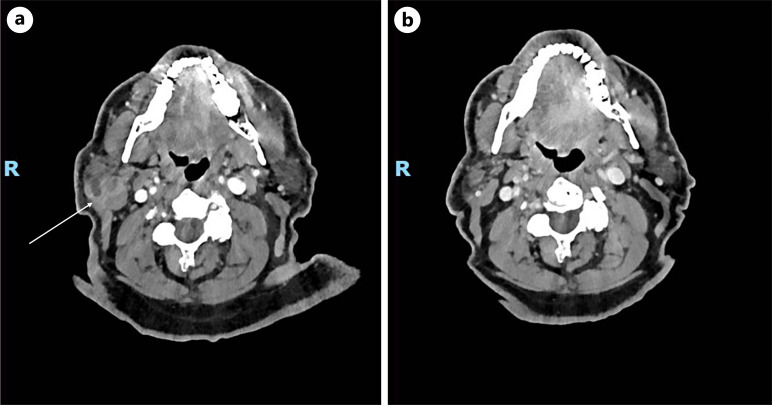

Case presentations: We describe two cases: first, HS in a 60-year-old man with primary tumor in the right anterior lower limb, and second, IDCS in an 82-year-old man in the right para-parotid region after initial wide local excision of a right postauricular mass suggestive of a pleomorphic undifferentiated sarcoma. Systemic imaging showed retroperitoneal, inguinal, and pelvic adenopathy in the first case and no distant metastases in the second case. Both were diagnosed via biopsy with extensive immunohistochemistry and were also found to be strongly positive on PDL1 testing. Treatment was initiated with ICIs in both patients, which was paired with palliative radiotherapy for the HS patient. Both cases exhibited a durable response to treatment upon repeated systemic imaging.